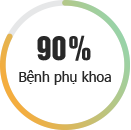

BỆNH PHỤ KHOA

Những bệnh lý ở “vùng kín” có thể đe dọa nghiêm trọng đến tâm lý, đời sống và đặc biệt là sức khỏe sinh sản của người phụ nữ. Đừng bao giờ chủ quan với các bệnh lý phụ khoa mà hãy khám và chữa bệnh kịp thời tại Phòng khám Đa khoa Quốc tế HN